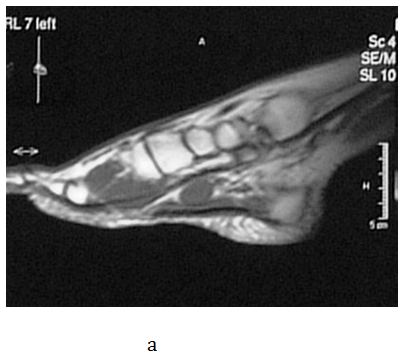

The operative and postoperative period passed without complications but she continued to have the same problems after the surgery. The patient received analgesic medications few months before she came to our Clinic. On her first visit at our outpatient clinic in July 2008, orthopedic shoes made on a plaster model of her feet with metatarsal pad were prescribed. On the control examination, the patient complained that the symptoms were worse and even disabling. An urgent MRI of the left foot was advised. The MRI showed a 2.5-centimeter in diameter, round, encapsulated mass that was differentially diagnosed as lipoma or neuroma (Figure 1a-1d). A surgical extirpation of the tumor was suggested. The operation was performed in September 2009 at the University Clinic for Orthopedic Surgery. At the level of the medial cuneiform bone of the foot, a round encapsulated mass, surrounding the medial communicant branch of medial plantar nerve was found (Figure 1e). Since the tumor could not be detached from the nerve, a neurectomy of the nerve proximal to the tumor was done. There were no complications in the operative and postoperative period. The excised tissue was sent for histological examination and the result confirmed it to be a Schwannoma (Figure 1f). After surgery, the patient was relieved of all symptoms. Follow-up visits were carried out at three, six and twelve months after the excision of the  Schwannoma. The patient had no pain and function of the left foot was normal at each consecutive control.

Figure 1 a, b) MRI cross section of the foot in T1 and T2 sequence (arrow shoving Schwannoma), c, d) MRI transverse section of the foot in T1 and T2 sequence e) macroscopic appearance of excised and cut in half Schwannoma f) Verocay body surrounded by Anthony B cells (HE, x100).